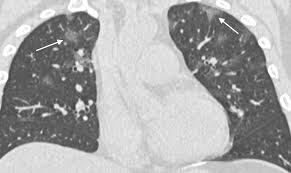

RSNA Journals